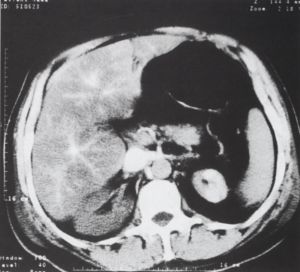

6, ábra.

A vesék alsó pólusának magasságában ábrázolódik a mérsékelten megnagyobbodott aorta tágulat, aneurysma, amelynek bal oldali részén az állumen hipodenz, thrombotizált. A jobb vese halmozza a kontrasztanyagot, a bal a. renalis az állumenből ered, ezért a bal vese keringése károsodott. A tág bélkacsokban folyadéknívó van (ileus).